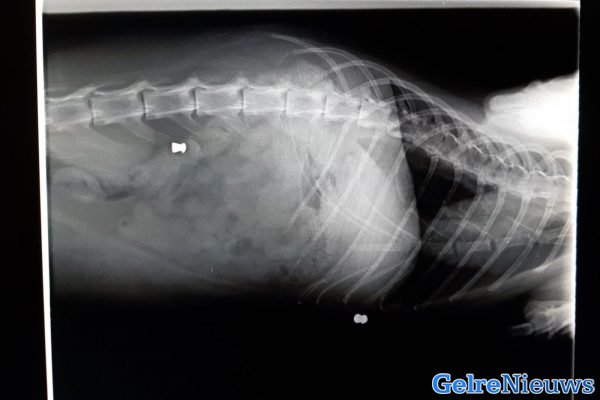

Maandag ging de eigenaresse met de kat terug omdat het nog steeds niet beter ging met het beestje. Bij de dierenarts is een foto gemaakt van de kat en daar bleek dat de kat is beschoten, de kogels zaten nog in zijn lijf. De eigenaresse vermoedt zelf dat het gebeurd is in de buurt van de Dr. Kuyperstraat en de Lindelaan. Dit zou dan gebeurd moeten zijn op vrijdagavond, zaterdagnacht of -ochtend voor 10:30 uur.

‘Zodra de kogels eruit zijn, ga ik aangifte doen’, aldus de eigenaresse. ‘Naar verwachting gebeurd dit dinsdag en dan is het hopen dat het verder geen vitale organen geraakt heeft.’